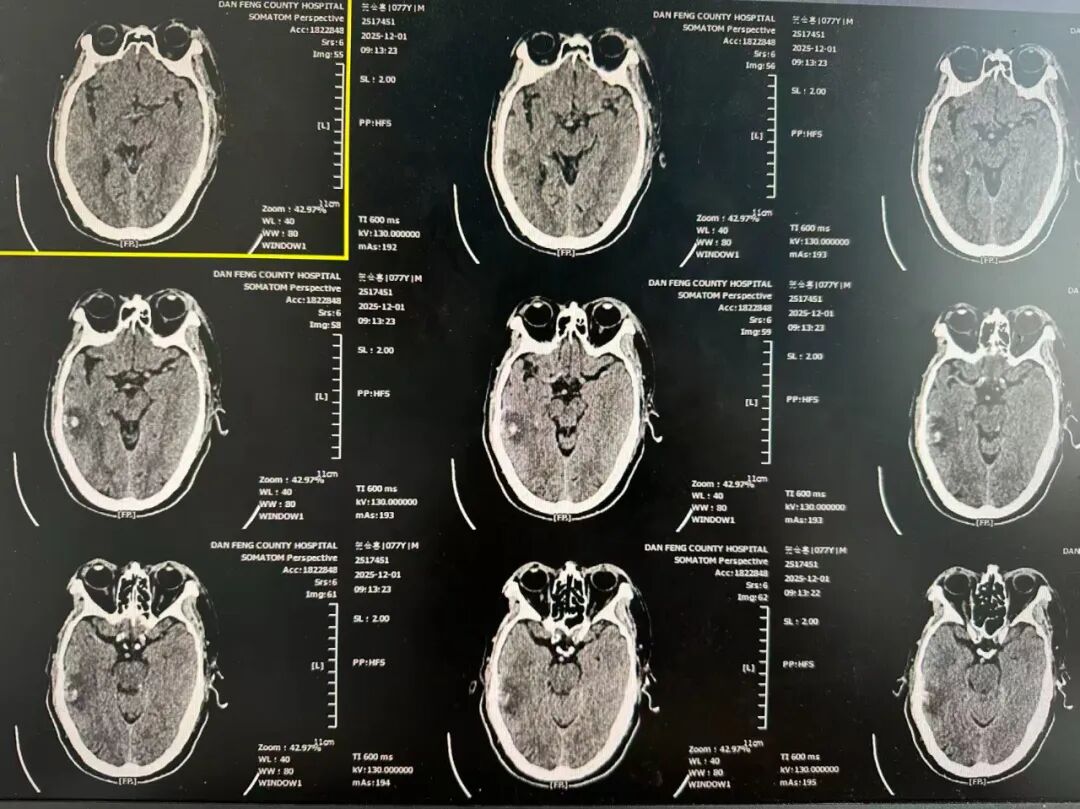

本次多学科讨论中,神经泌尿外科医师淡增增详细汇报了病例资料。患者男,64岁,因“车祸外伤后全身多处疼痛2小时”主诉于2025年12月6日19:30入院。入院诊断:1.急性中型闭合性颅脑损伤 创伤性蛛网膜下腔出血;2.胸部闭合性损伤 多发肋骨骨折 创伤性湿肺 血气胸;3.腰椎爆裂骨折;4.胸椎骨折;5.下颌骨髁突骨折;6.吸入性肺炎;7.应激性溃疡。